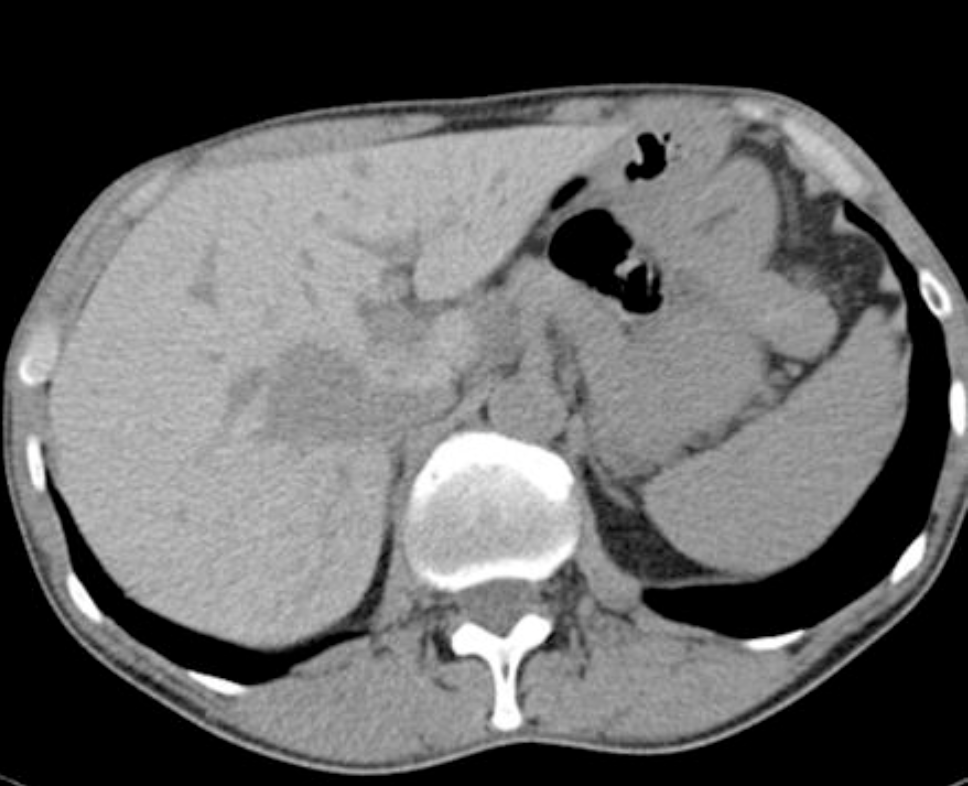

Most common cause of this?

“Double duct” sign = pancreatic adenocarcinoma at the pancreatic head.